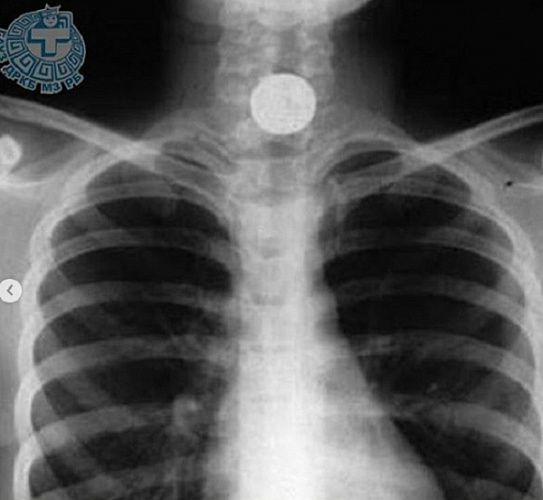

Из пищевода 10-летнего улан-удэнца извлекли монету

В Детскую республиканскую клиническую больницу поступил 10-летний улан-удэнец, который случайно проглотил 10-рублевую монету. Об этом случае рассказали на странице больницы в Instrgram.

Ребёнку срочно провели рентгенографию: да, монета визуализируется, её ничем не спутаешь, сидит в верхней трети пищевода. Мальчик рассказал, что и как произошло. Ребёнка отправили на эндоскопию. Дежурный врач, эндоскопист, Зорик Хангалов объяснил ребёнку, что он будет сейчас делать и как надо себя вести. Мальчик перенёс процедуру спокойно.

- Монета чётко видна в эндоскоп, однако удалить её не удается из-за выраженного спазма пищевода. Бывает, что у детей этого возраста спазм не выражен и подобные инородные тела удаляются с первого раза. В данном случае, чтобы удалить его без травмирования пищевода, Зорик Владимирович счёл необходимым повторить попытку под кратковременным наркозом, - сообщили в больнице.

В хирургическом отделении мальчика осмотрел врач-анестезиолог, оценивая состояние, чтобы дать адекватное обезболивание. На помощь Хангалову приходит опытный врач-эндоскопист Марина Ровкина. Вместе они без труда удаляют монету из пищевода ребёнка.

Операция прошла быстро. После пробуждения от наркоза юный пациент уже через несколько часов был весел и активен. Мальчик с мамой переночевали в больнице, а на утро отправились домой.